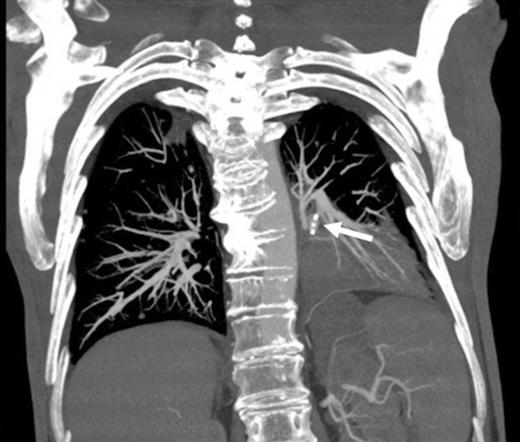

Selective digital subtraction angiography image of left lower lobe pulmonary artery, demonstrating filling of the inflammatory aneurysm and depicting the feeding branches clearly

Digital subtraction angiography post deployment of the AVP 4 device in the PA branch feeding the aneurysm (arrow). No residual or collateral filling seen